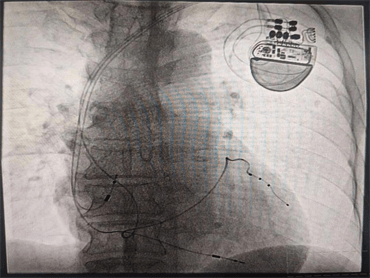

8月9日晚,心血管內(nèi)科九病區(qū)崔旭輝主任團(tuán)隊(duì)成功開展了CRT-P(簡稱三腔起搏心臟再同步化起搏器)。該手術(shù)成功實(shí)施,為此類患者的治療提供了一個(gè)新的保障,也標(biāo)志著我科心力衰竭介入治療技術(shù)又上了一個(gè)新臺(tái)階,具有重大意義。

由于患者心功能差,身材消瘦,且情緒較為焦慮,術(shù)后易伴并發(fā)癥,心血管內(nèi)科九病區(qū)醫(yī)療團(tuán)隊(duì)針對(duì)該患者的情況進(jìn)行術(shù)前討論研究,護(hù)理團(tuán)隊(duì)采用敘事護(hù)理的方法解除了患者的焦慮情緒,在充分考量患者的個(gè)體因素后,經(jīng)患者及家人同意,確定手術(shù)方案。術(shù)中,崔主任親切的語言緩解了張大爺?shù)慕箲],在平靜的狀態(tài)下成功將三個(gè)電極植入到右心房、右心室、左心室(冠狀靜脈分支遠(yuǎn)端)圓滿完成了手術(shù)。術(shù)后,反復(fù)程控參數(shù),達(dá)到起搏器工作狀態(tài)最優(yōu)化,復(fù)查心電圖示QRS波恢復(fù)到107ms,明顯變窄,患者心臟功能及癥狀較手術(shù)前顯著改善,遠(yuǎn)期療效在進(jìn)一步觀察中,將通過不斷程控,優(yōu)化心臟起搏器參數(shù),達(dá)到更好的治療效果,崔主任親自為患者按時(shí)換藥,術(shù)后切口愈合良好。通過護(hù)士長魏薇及護(hù)理團(tuán)隊(duì)的精心指導(dǎo),張大爺術(shù)后的康復(fù)鍛煉也非常順利。

心臟再同步化治療(CRT或者CRT-P)是近年來發(fā)展迅速的治療心力衰竭患者的重要手段,它是將電極植入右心房、右心室及左心室三腔起搏,使左右心室同步激動(dòng),同步收縮,改善心臟功能,降低心力衰竭患者病死率,是心力衰竭者的新希望,是心力衰竭治療史上一個(gè)里程碑的突破。